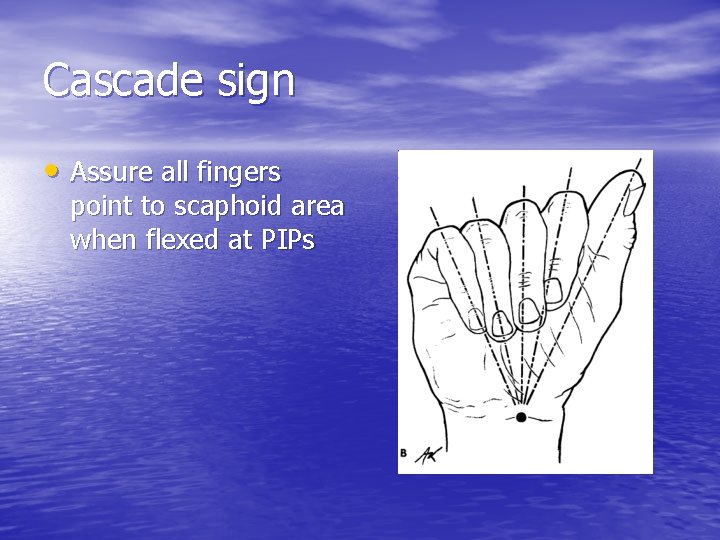

Cascade sign • Assure all fingers point to scaphoid area when flexed at PIPs